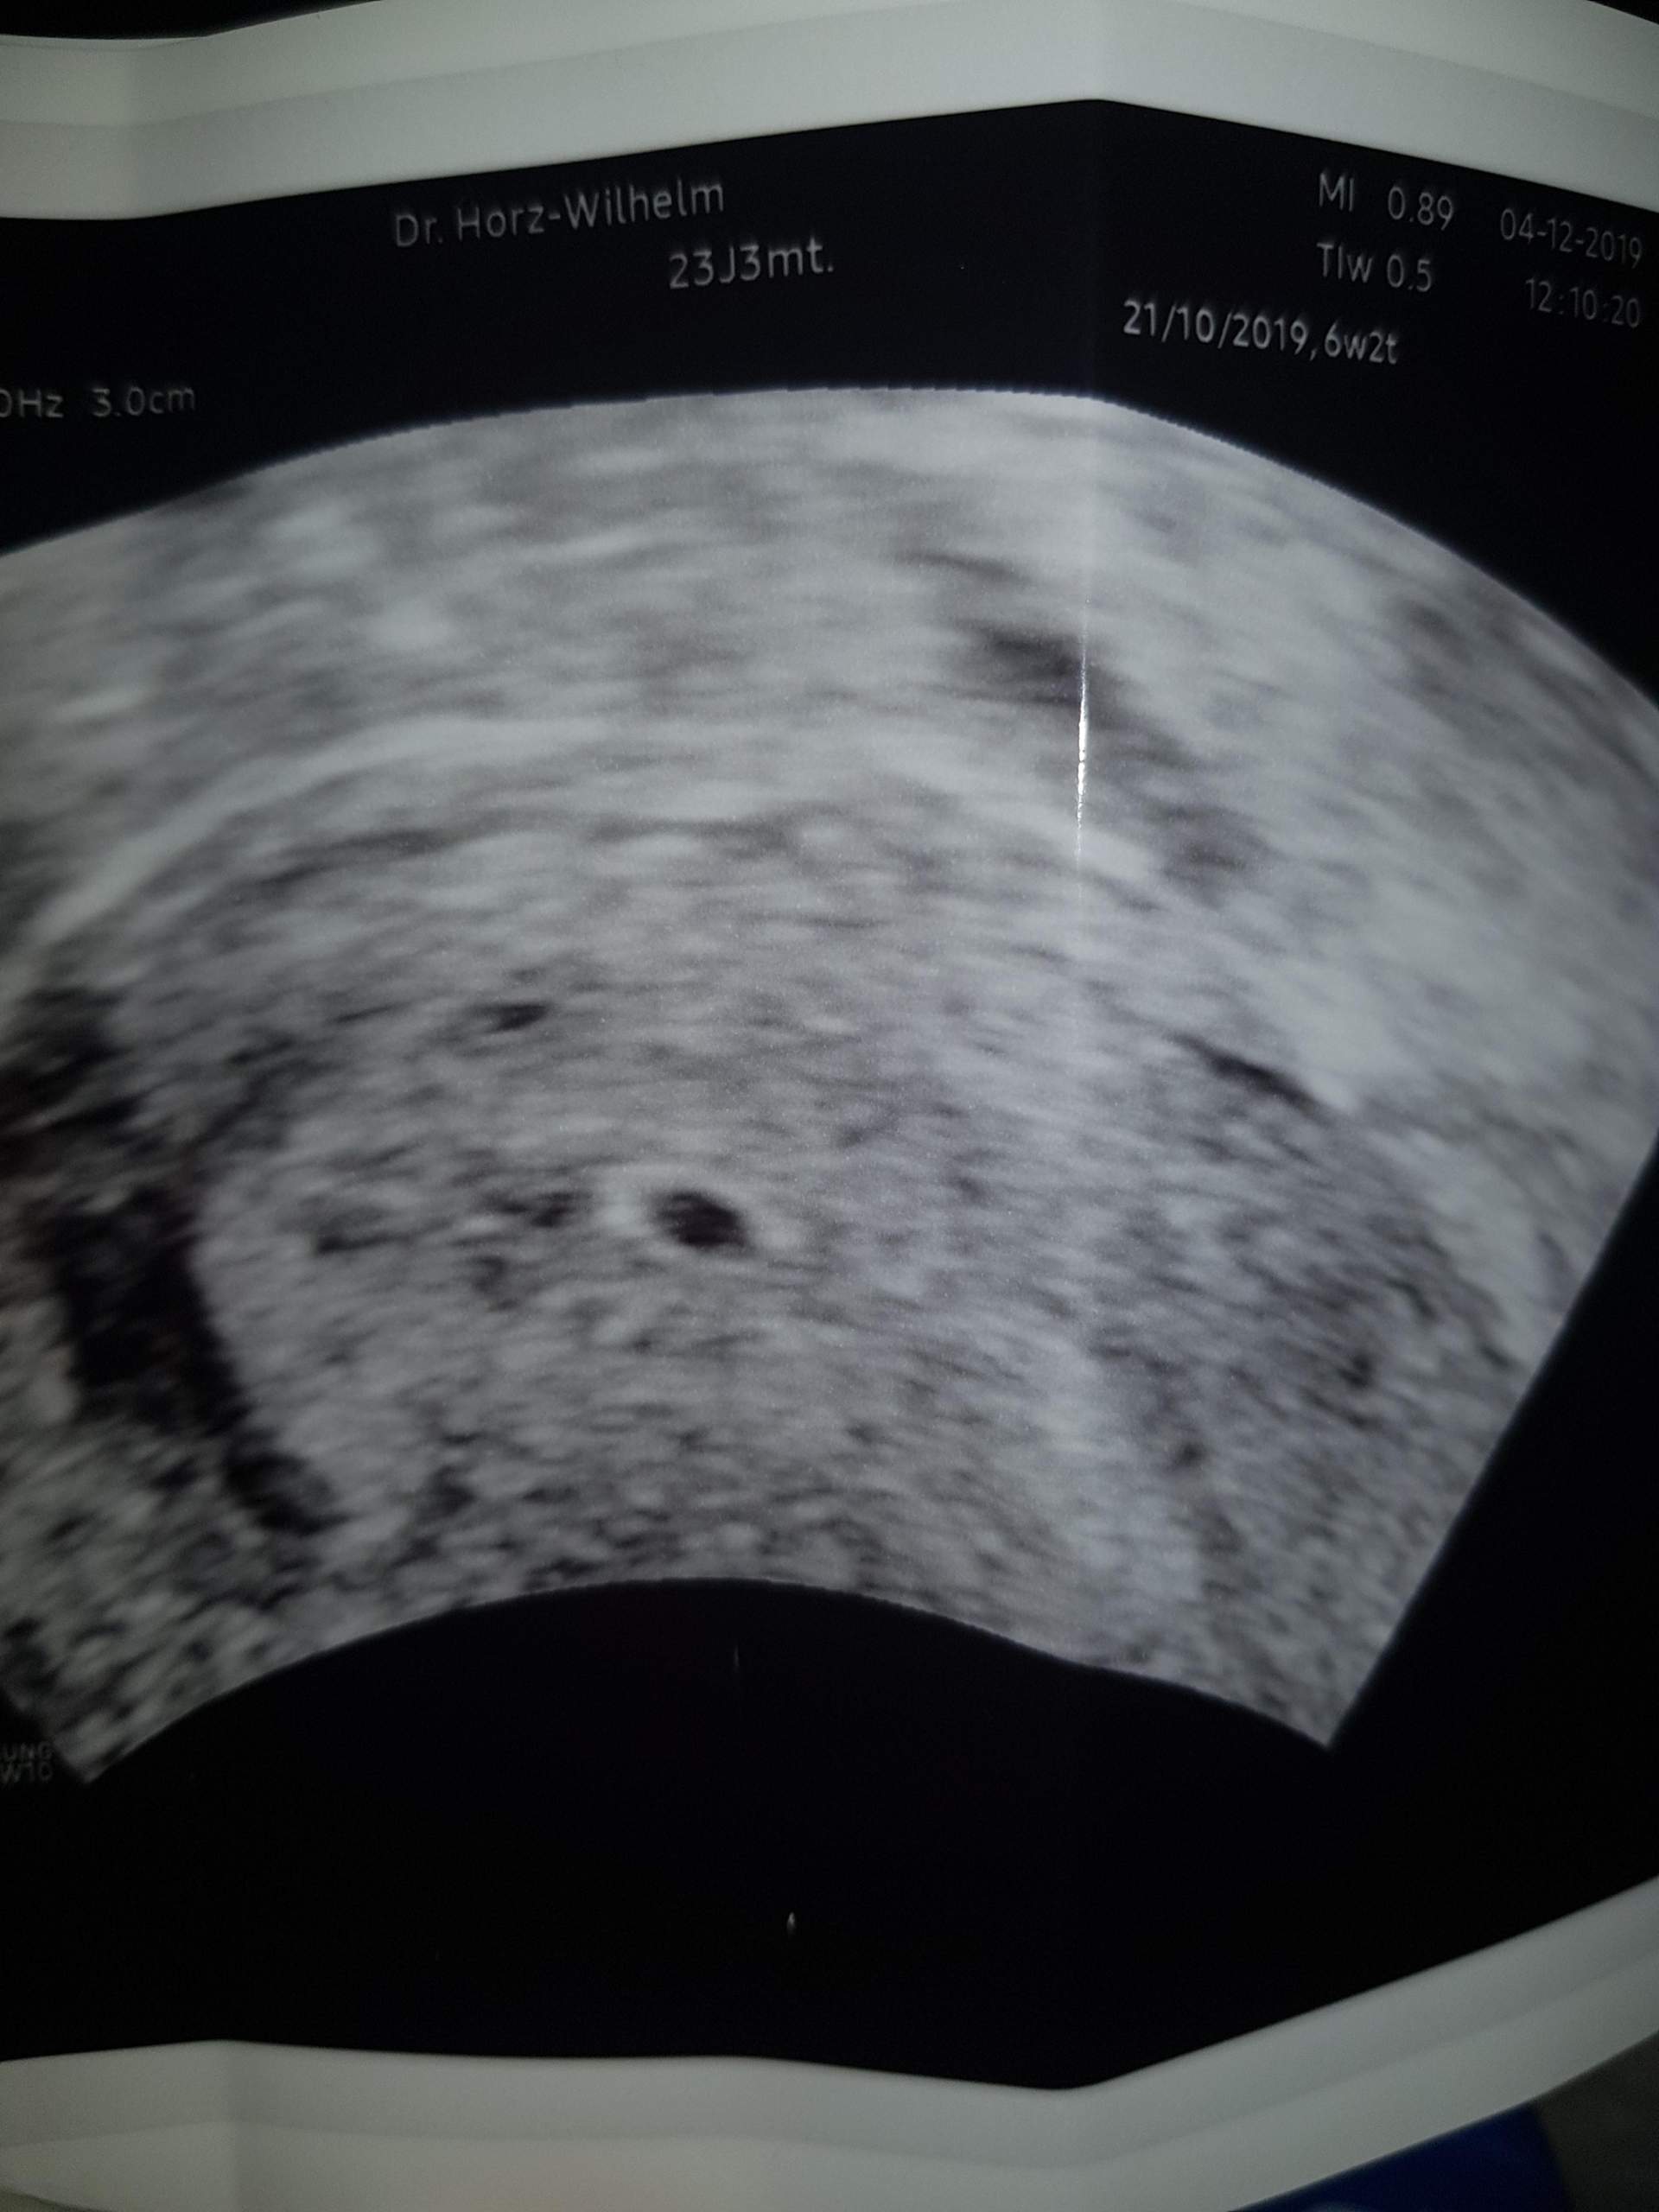

SSW können sich erste frühe Schwangerschaftsanzeichen bemerkbar machen. Kriminalhauptkommissar Henry Koitzsch und Kriminalkommissar .Das entspricht etwa der 4. In den meisten Fällen hilft deshalb ein klärendes Gespräch mit dem behandelnden Arzt, die Angst und den .Unterleibsschmerzen in der 4. Momentan auch wieder. Der Frauenarzt kann außerdem noch die gut aufgebaute Gebärmutterschleimhaut (Endometrium) erkennen, die den Nährboden für den Embryo bildet.Das ungeborene Leben verankert sich in der 4.

Unterleibsschmerzen können als Ziehen, Druck, Stechen oder Brennen empfunden werden. Das liegt daran, dass dein Darm unter dem Einfluss der . Schwangerschaftswoche kommst, beginnt .Wenn es um den Umgang mit Unterleibsschmerzen in der 6. im Abdomen, auftreten.Polizeiruf 110 ∙ MDR-Fernsehen. Schwangerschaftswoche können Vor- und Senkwehen auftreten. SSW Unterleibsschmerzen wie bei der Periode auftreten, muss das nicht sofort ein Anzeichen dafür sein, dass etwas nicht in Ordnung .6 ssw (5+0) Unterleib schmerzen.2021, 21:35 Uhr.deEntzündung im Unterleib – Dr-Gumpert. Während des 2. Wenn Du ein leichtes Ziehen im Unterleib spürst, kann dies ein erstes Anzeichen für eine Schwangerschaft sein.Bereits in der 4. SSW (4+0 bis 4+6) ist dein Baby rund eine Woche alt, die Schwangerschaft besteht rein rechnerisch aber schon seit drei Wochen, da die ersten zwei Wochen deines Zyklus vor dem Eisprung mitgezählt werden. Für Außenstehende ist eine Veränderung bisher aber normalerweise noch nicht erkennbar.deEmpfohlen auf der Grundlage der beliebten • Feedback SSW\n: 1,5 cm – Entwicklung der . Grundsätzlich gilt: . Ich hatte schon vorher .Unterleibsschmerzen während der Schwangerschaft können verschiedene Ursachen haben und sind oft harmlos, wie z. Der Grund dafür ist logisch: Das Wachstum von Uterus und Kind belastet Muskeln, Bänder und Organe.Unterleibsschmerzen vorbeugen und lindern. Falls Deine Periode ausbleibt oder Du schon eine . SSW im Ultraschall erkennt.

unterleibsschmerzenPlötzliche Unterleibsschmerzen können aus vielen Gründen auftreten, einschließlich Entzündungen, zyklusbedingte Schmerzen, Verletzungen, Endometriose, Eierstockzysten, Blinddarmentzündung und anderen gynäkologischen Problemen. Nur ein schwarzer Fleck, der die Fruchthöhle zeigt, ist sichtbar.deUnterleibskrämpfe – Ursachen und Therapie – Heilpraxisheilpraxisnet. Diese sind zum Teil auf die Veränderungen in deiner Gebärmutter zurückzuführen.Ein häufiges Symptom ist ein leichtes Ziehen im Unterleib .